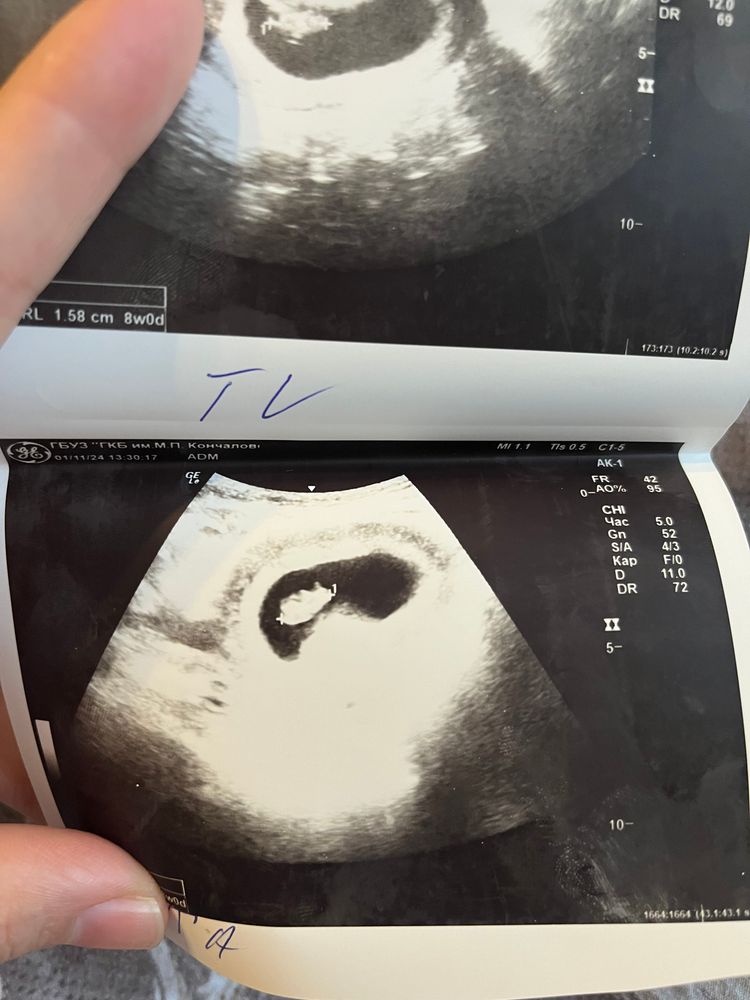

Алена, 8 -недель Изображение

03.12.2024

Зарина Тохирова, мальчик )